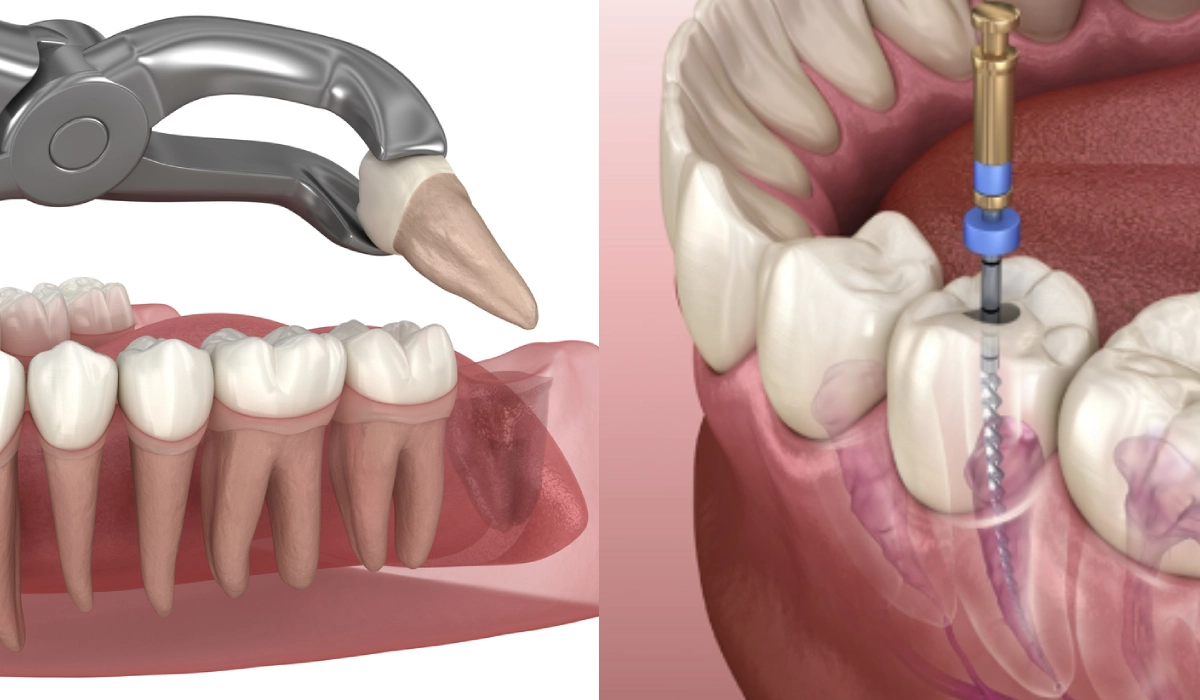

A root canal can be likened to a surgical rescue mission, meticulously designed to retrieve a tooth from the clutches of decay. In this procedure, an endodontist elegantly removes the inflamed or infected pulp tissue from the inner sanctuary of the tooth. After decontamination, the chamber is filled with a biocompatible material, and a crown may be placed on top to fortify the tooth’s structure. Here are some compelling facets to consider:

Tooth Extraction: A Decisive Farewell

On the opposite end of the spectrum lies tooth extraction, akin to decluttering an overburdened space. Removal is often considered when a tooth is deemed irremediable, either due to extensive decay, advanced periodontal disease, or irreparable fractures. The allure of this route lies in its decisiveness. Here are salient points to consider about extraction:

- Swift Resolution: Tooth extraction is typically a more straightforward and faster procedure, delivering immediate relief from pain and discomfort.